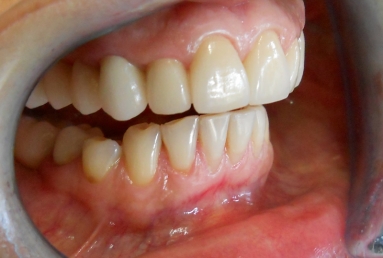

After treatment:

– zirconium/ceramic bridge in the lateral right maxillary area

– two implants and zirconium/ceramic bridge in the lateral left maxillary area

– full ceramic individual crowns in the frontal maxillary area, correcting at the same time the occlusion and the position of the frontal teeth.

– the lower arch was restored with a zirconium/ceramic bridge in the lateral right area and composite esthetic fillings + teeth whitening for the rest of the natural teeth.